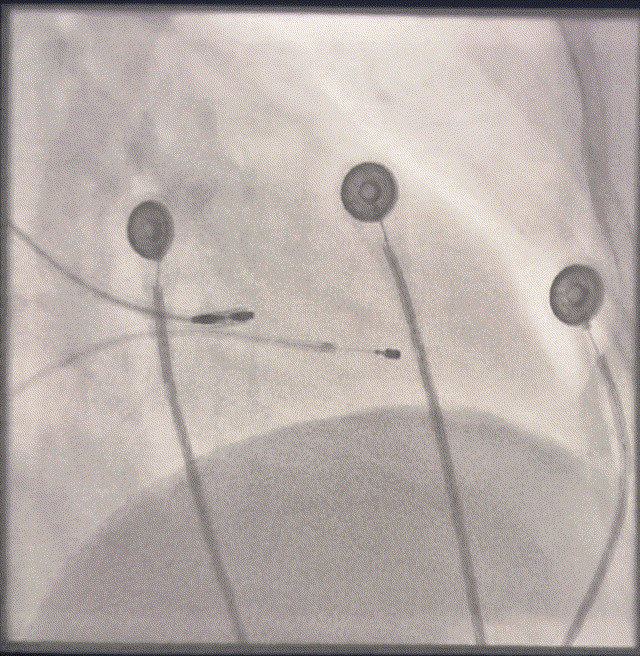

定位左束支

图3